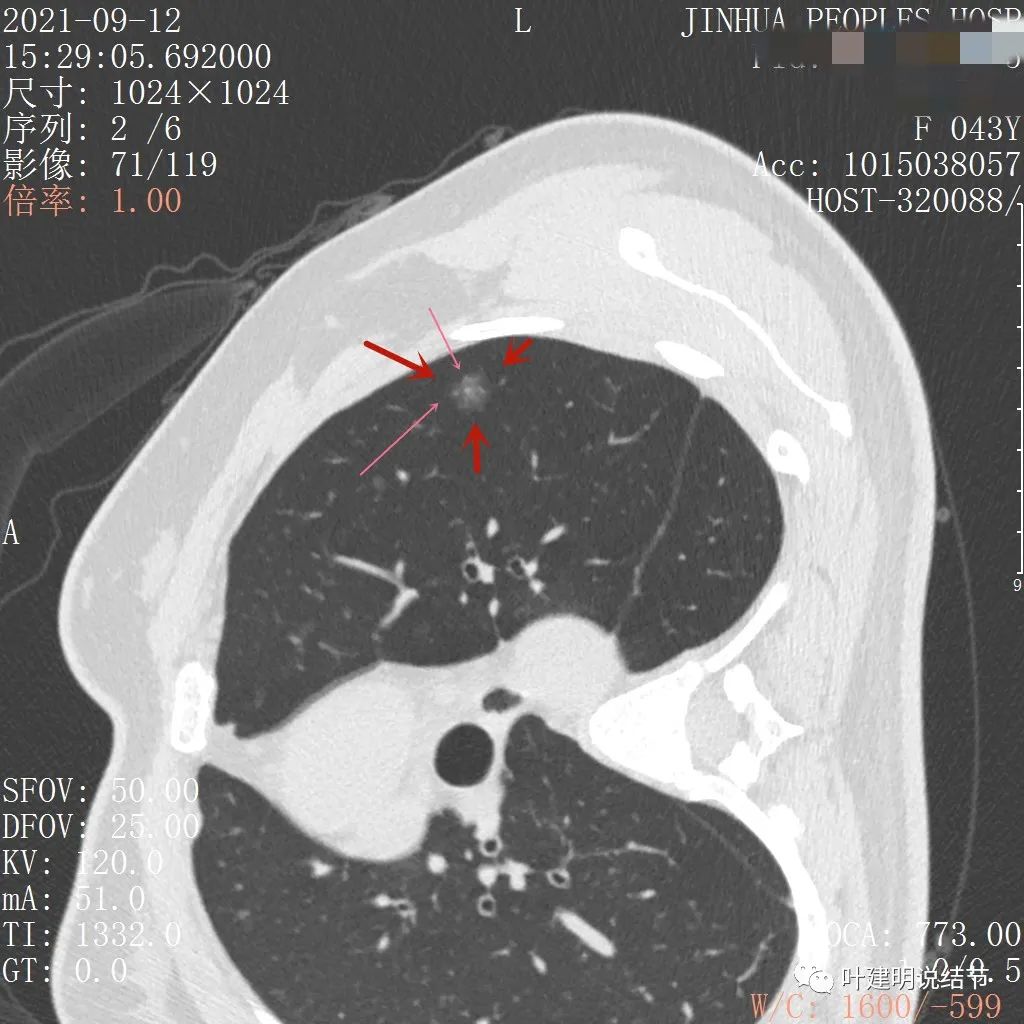

上图显示混合磨玻璃结节,中间点状高密度区域,边上有微小血管征

上图示病灶边缘磨玻璃成分有的区域密度过低(绿色箭头),事后回头来看,磨玻璃部分的密度过低,不容易是浸润性腺癌,而更符合原位腺癌

上图示瘤肺边界处显模糊(砖色箭头),病灶内部仍是有偏高密度的点状成分